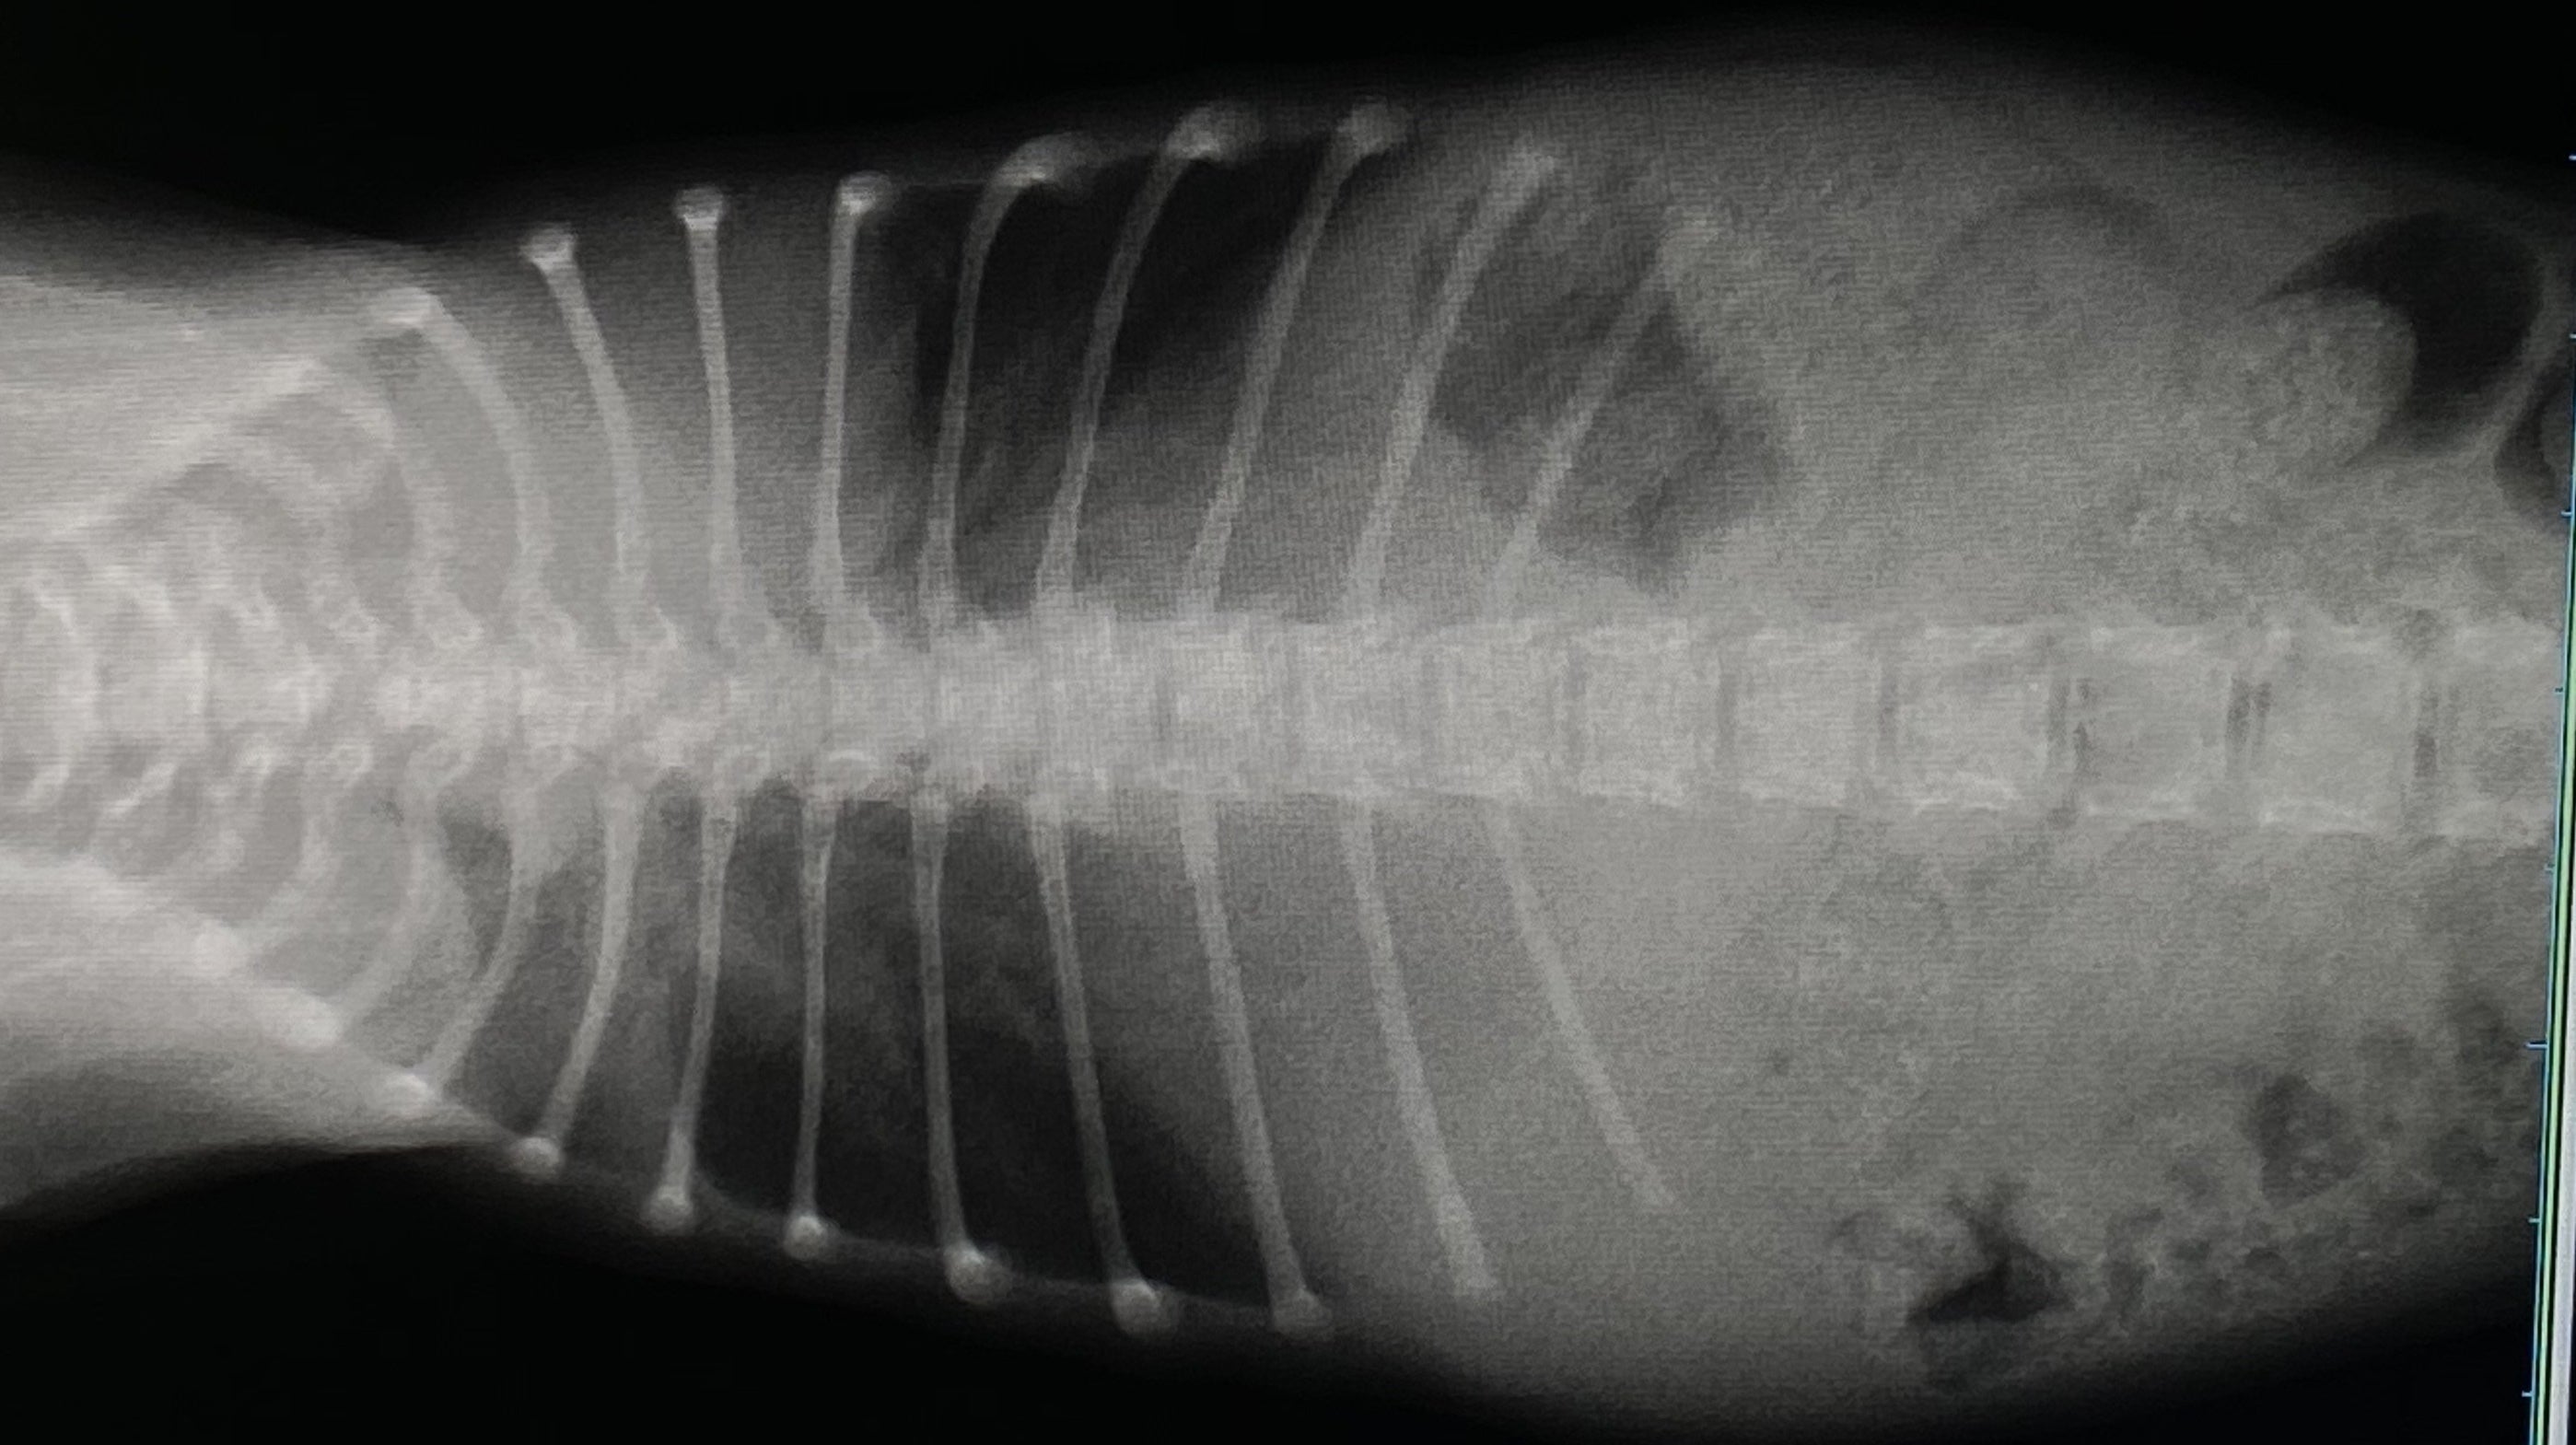

レントゲンを見た感じだと肋骨が内蔵(心臓)にくい込んでいる(通常じゃ有り得ないことなのでまだ未確定)可能性があり手術の難度も上がり、費用も通常よりもかなり高額になるとの事です。

肋骨も庇うためか歪んでしまっていました。。

肺も小さいので肺活量がかなり少なく、すぐにバテて動けなくなります…